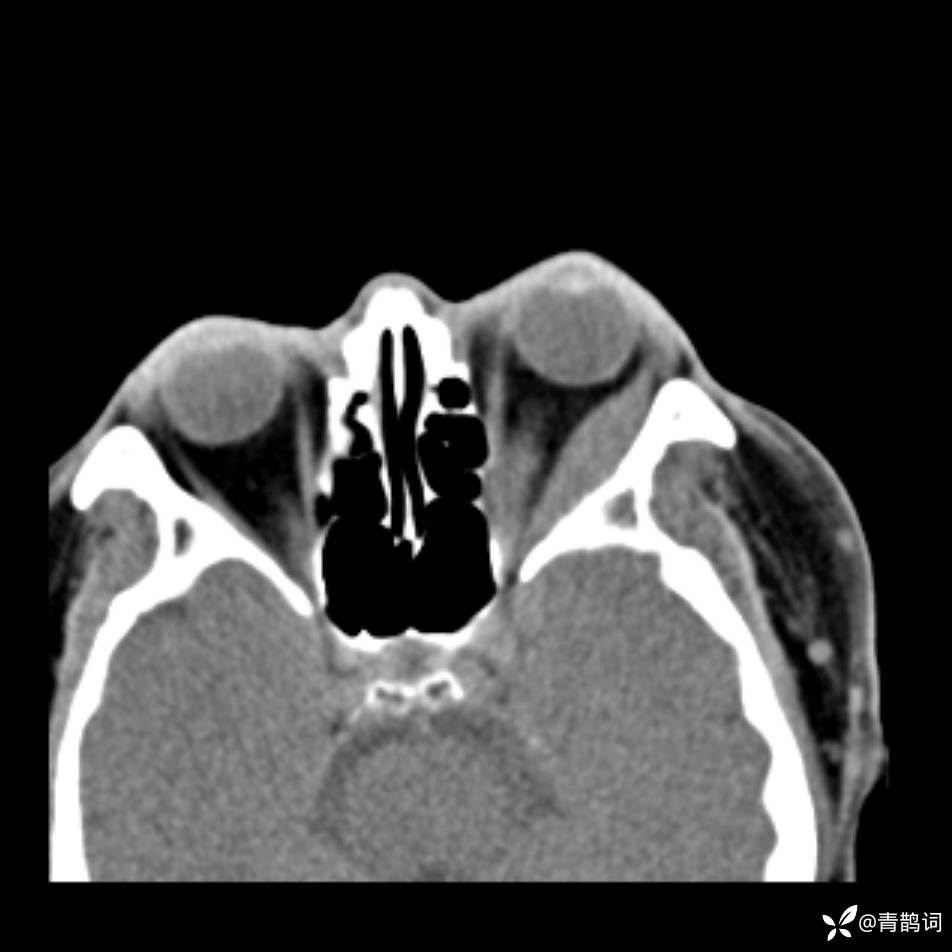

患者年龄:30岁。

患者性别:男。

简要病史:左颜面部肿胀2年,反复咳嗽咳痰,逐渐加重。

结合病史及影像学表现,期待评论区各位老师各抒己见~